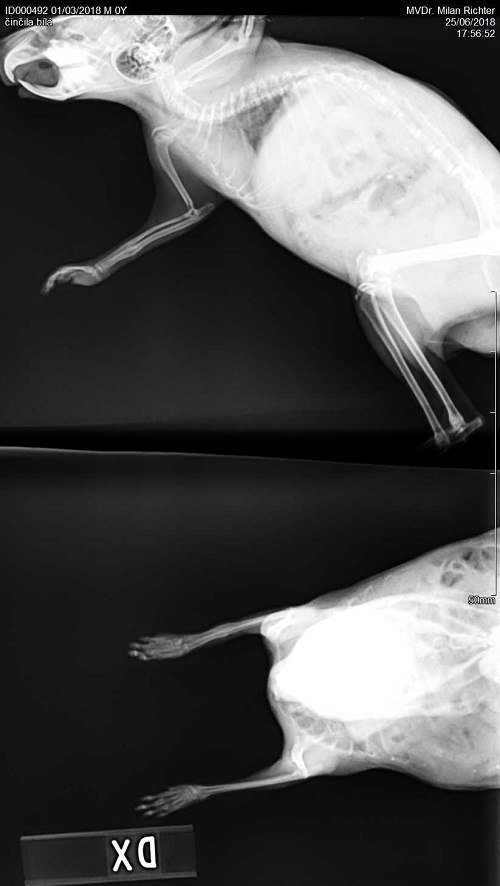

Velmi komplikovaná fraktura obou předloketních kostí u drobné činčily, jelikož se tak drobné implatáty běžně nevyrábějí, řešili jsme ji implantací nitrodřeňových hřebů vyrobených z injekčních jehel. Pacient se kompletně a bez následků uzdravil, po vyjmutí hřebů nožičku naplno používá.